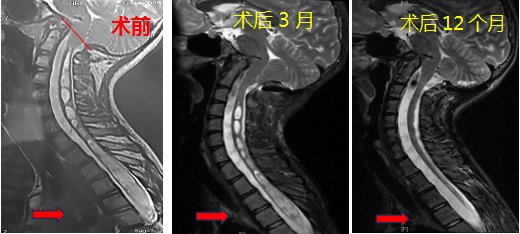

最后,小脑扁桃体下疝畸形的预后如何呢?对于无症状无脊髓空洞的病人,可能一辈子带病生存无任何影响。对于无症状有脊髓空洞以及有症状无论有无脊髓空洞的病人,不做手术基本都会逐渐恶化加重,而手术则可阻断进展而且至少有80%以上的改善,如下图。

6微信图片_20240906190859.png